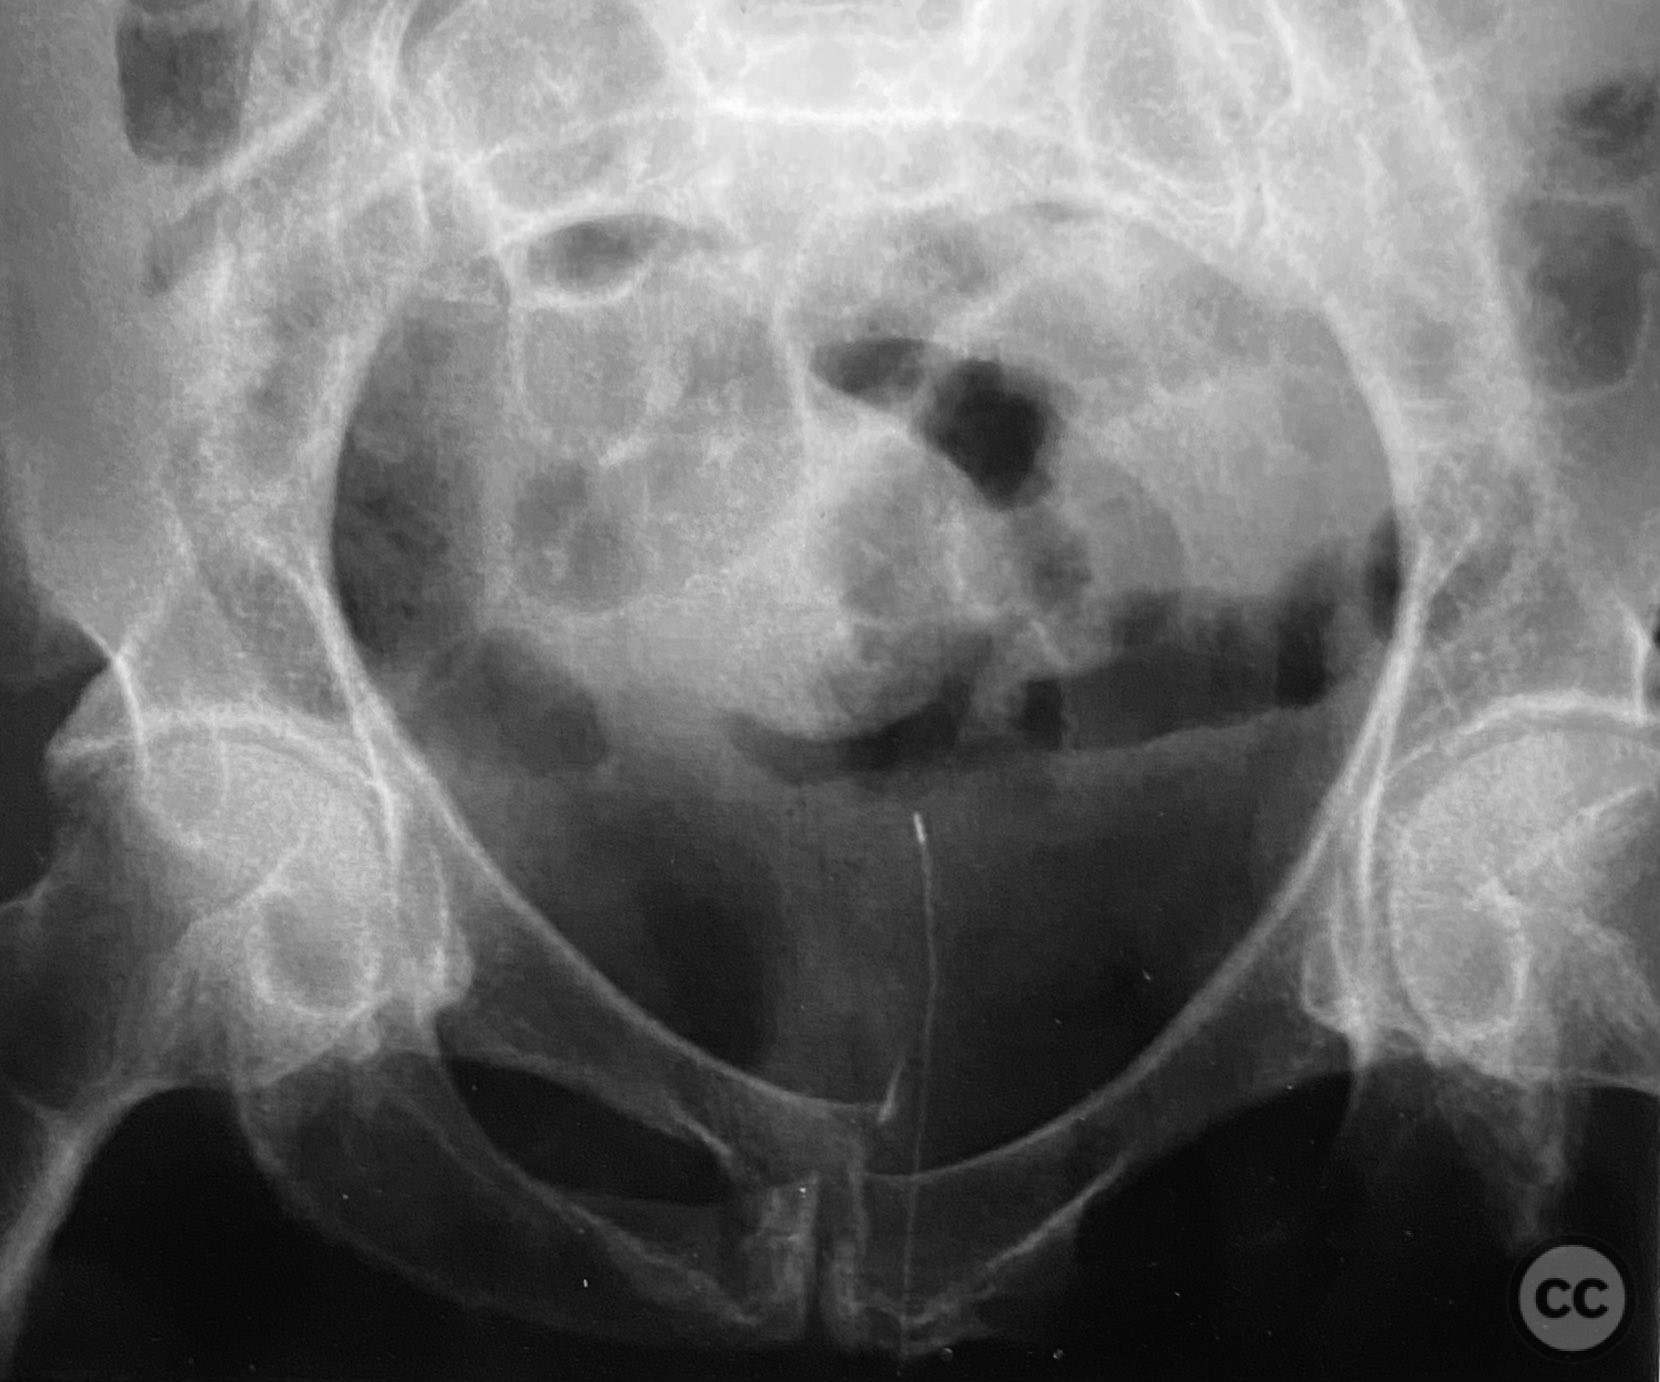

Clinical and radiological findings:  Adult patient presenting with severe pelvic pain, unable to sit or transfer to a chair. Clinical examination under anesthesia demonstrated pelvic instability with “rebound reduction” upon minimal iliac crest compression. Imaging revealed an unstable superior pubic ramus fracture with challenging anterior pelvic bone anatomy and dense cortical bone at the anterior acetabular wall.

Planning remarks:  Planned trans-symphyseal fixation of the superior pubic ramus fracture using a 4.5mm cortical screw, with preoperative intent to maximize implant purchase in stable bone regions. Surgical approach selected to facilitate direct access to the superior pubic ramus and symphysis pubis.